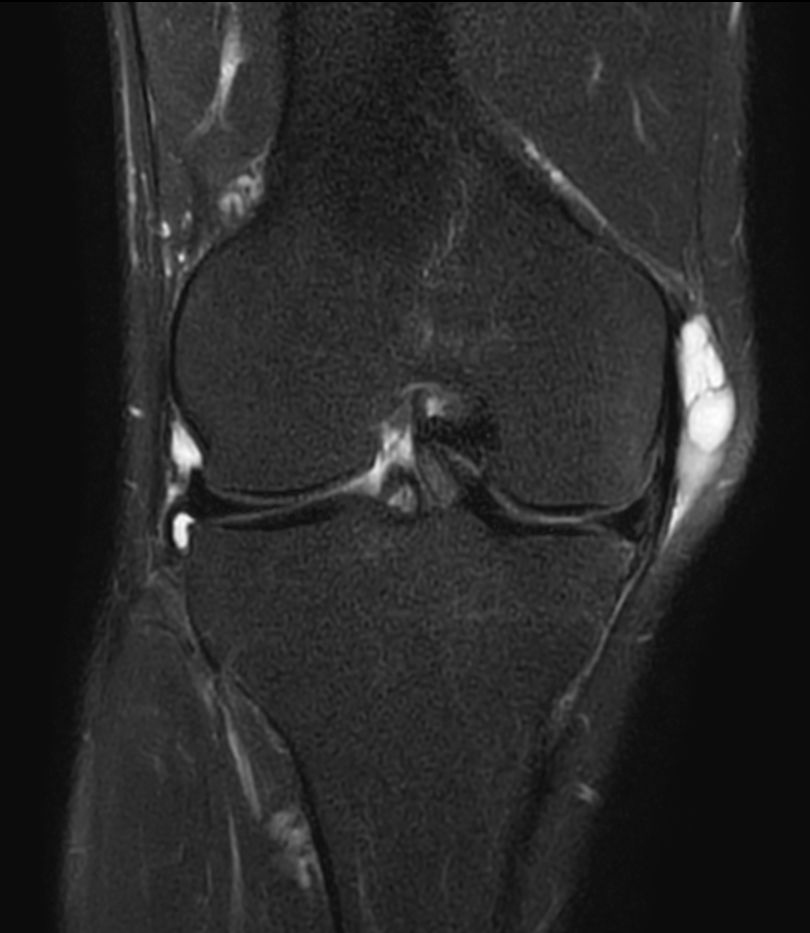

T2w TSE FatSat - Compressed SENSE